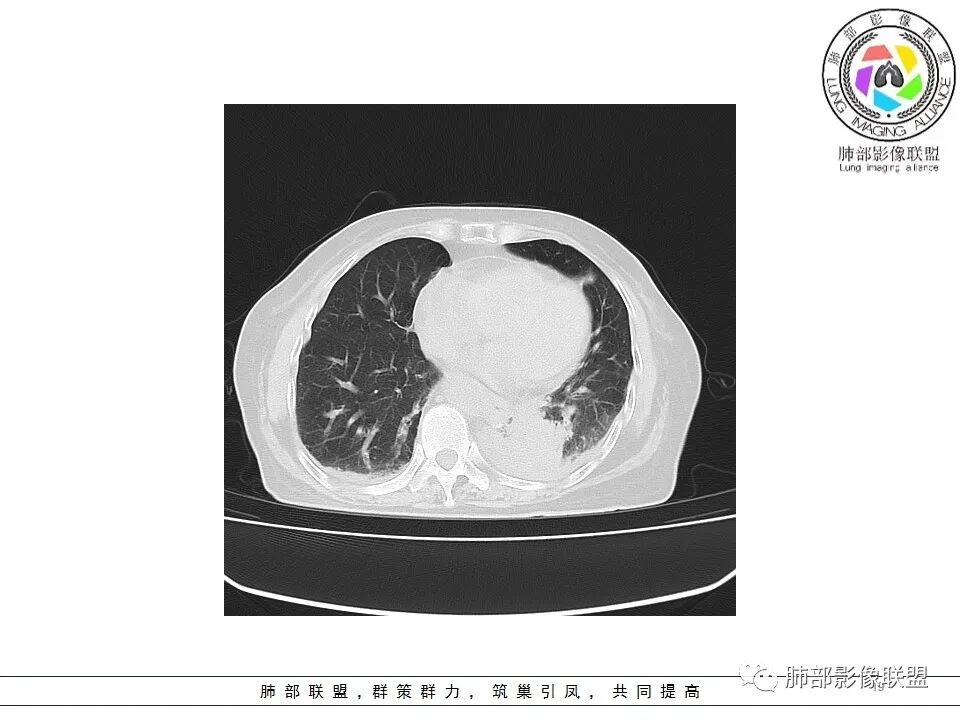

一切∮随缘: 左肺下叶脊柱旁可见大片状实变,跨多个叶段,宽基底与胸膜相贴,胸膜下可见积液,周围伴有空洞,平扫密实欠均匀,增强扫描可见低密度坏死,及血管束穿行,临床:女性,反复咳嗽咳痰7天,余未提示异常,无实验室指标,考虑:慢性脓肿(OP),放线菌?奴卡?腺癌?完善支气管镜,穿刺送培养,病理学检查。

春秋.: 老年女性,左肺下叶团状致密影及胸腔积液,强化不均匀,可见边界清晰坏死区及强化环,整体考虑炎性改变!

宇宙: 左肺下叶后基底段肿块,边缘毛糙,后基底段支气管阻塞,明显不均匀渐进强化,其内血管清晰自然,可见坏死灶,部分边界清,左侧胸水,考虑炎性病变,鉴别腺癌

飞鹰行动: 女,78岁,反复咳嗽,咳痰七天,左肺下叶纵膈旁团片状实变影,边界清晰,局部膨胀性生长,病灶内密度不均,增强扫描病灶内呈不均匀性强化,部分坏死区边界不清晰,内可见血管造影征,部分坏死区边界清晰,可见环形强化,感染性病变是有的,需要警惕合并占位,腺癌伴感染?

风儿: 老年女性,咳嗽咳痰7。左肺下叶后基底段肿块,边缘毛糙,外缘轻度膨隆,支气管有阻塞,强化不均匀,其内血管清晰自然,可见边缘清晰坏死灶,少量胸水,考虑:炎性-炎症机化伴慢性脓肿、放线菌;肿瘤:腺癌

尘缘: 老年女性,咳嗽咳痰7天,影像表现:左下肺肿块,内部多处坏死,胸腔积液,增强内部血管走行尚可,血管破坏不明显,大的坏死边缘清楚,大的坏死后面一部分不均匀强化,内部边界不规则的坏死,在肿块后方是强化的不张肺组织。思路:初步诊断:1,感染明确,依据,咳嗽咳痰七天,双肺渗出改变,胸腔积液,左下肺脓肿形成,查一下血象,CRP,PCT等炎性指标。2、左下肺肺癌可能较大,依据:大的坏死后面一部分强化不均匀,坏死边界不清,内部血管明显比其他部分减少。外围不张(常规来说腺癌可能更大,但是这个病人肿块外围有强化的不张肺组织,所以鳞癌高度怀疑),3、肺隔离症,这个部位要怀疑,但是提供的影像没有体动脉供血依据,需要结合血管重建明确。4、淋巴瘤,这种肿块伴坏死,胸腔积液的老年女性,要考虑弥漫大B的可能,需要穿刺病理明确。5、整个一元特殊感染,放线菌、结核等等,需要结合口腔清洁情况和NGS明确。综上所述:考虑肺癌(鳞癌>腺癌>其他类型癌)合并感染可能大,鉴别诊断:放线菌感染>淋巴瘤(弥漫大B)>肺隔离症>结核,下一步穿刺活检及NGS。

老年女性,急性发病,短病程病史。左肺下叶实变影,肺叶体积缩小,周围有带状不一致密度影。单独发生于左侧的胸腔积液渗出液多见。   影像上病灶重建后长轴呈楔形,而非类圆形,边缘平直,符合肺叶形态(与横断位膨隆并不一致),从整体形态上支持炎性病变;   病灶内血管走形自然,无受侵犯、受推移迹象,不大符合鳞癌等破坏性较强的肿瘤性病变。女性患者鳞癌也少见。   病灶内坏死腔内壁清楚光滑,薄环状强化带,支持炎性、尤其是化脓性病变。肺腺癌这样的坏死少见。   病灶近端支气管虽然堵塞,但是支气管走形自然,壁无明显破坏,腔内粘液栓堵塞为主,病灶外周大,内带小,局部无膨隆迹象,不符合近端支气管肺癌堵塞所致表现;也不符合外周肿块朝内带推进表现。   综合分析:符合炎性病变,不支持恶性肿瘤性改变